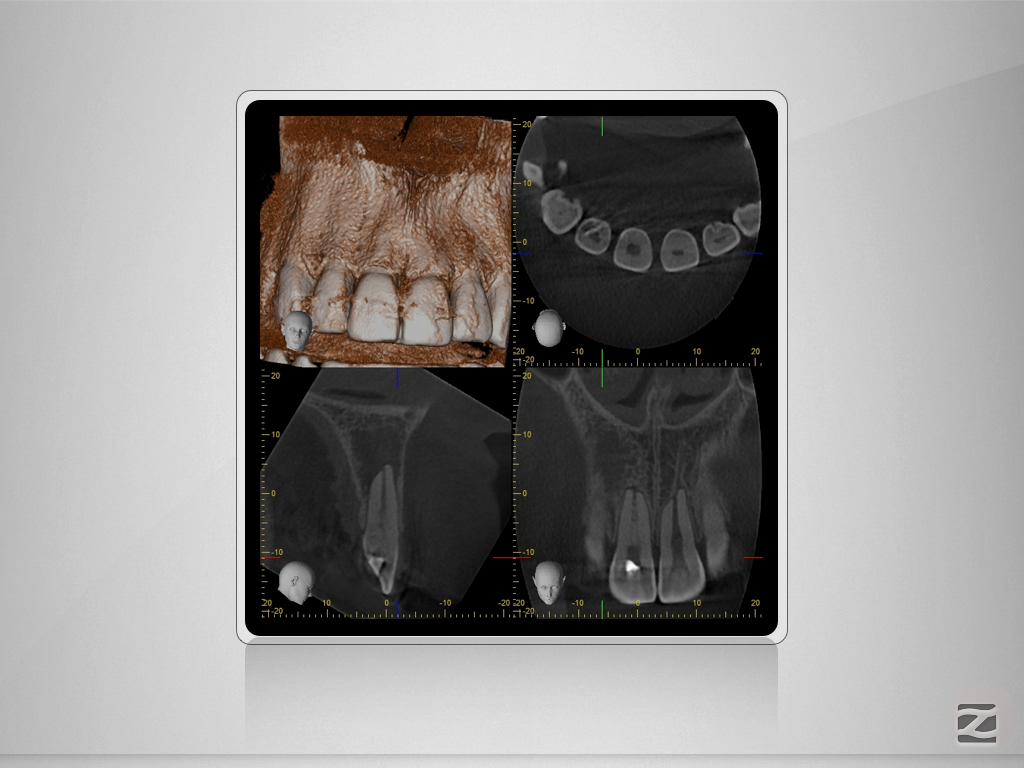

12 11 D.002

Invagination Typ 2 nach OEHLERS